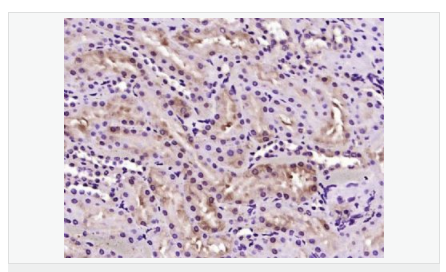

產(chǎn)品應用WB=1:500-2000 ELISA=1:5000-10000 IHC-P=1:100-500 IHC-F=1:100-500 ICC=1:100-500 IF=1:100-500 (石蠟切片需做抗原修復)

image.png